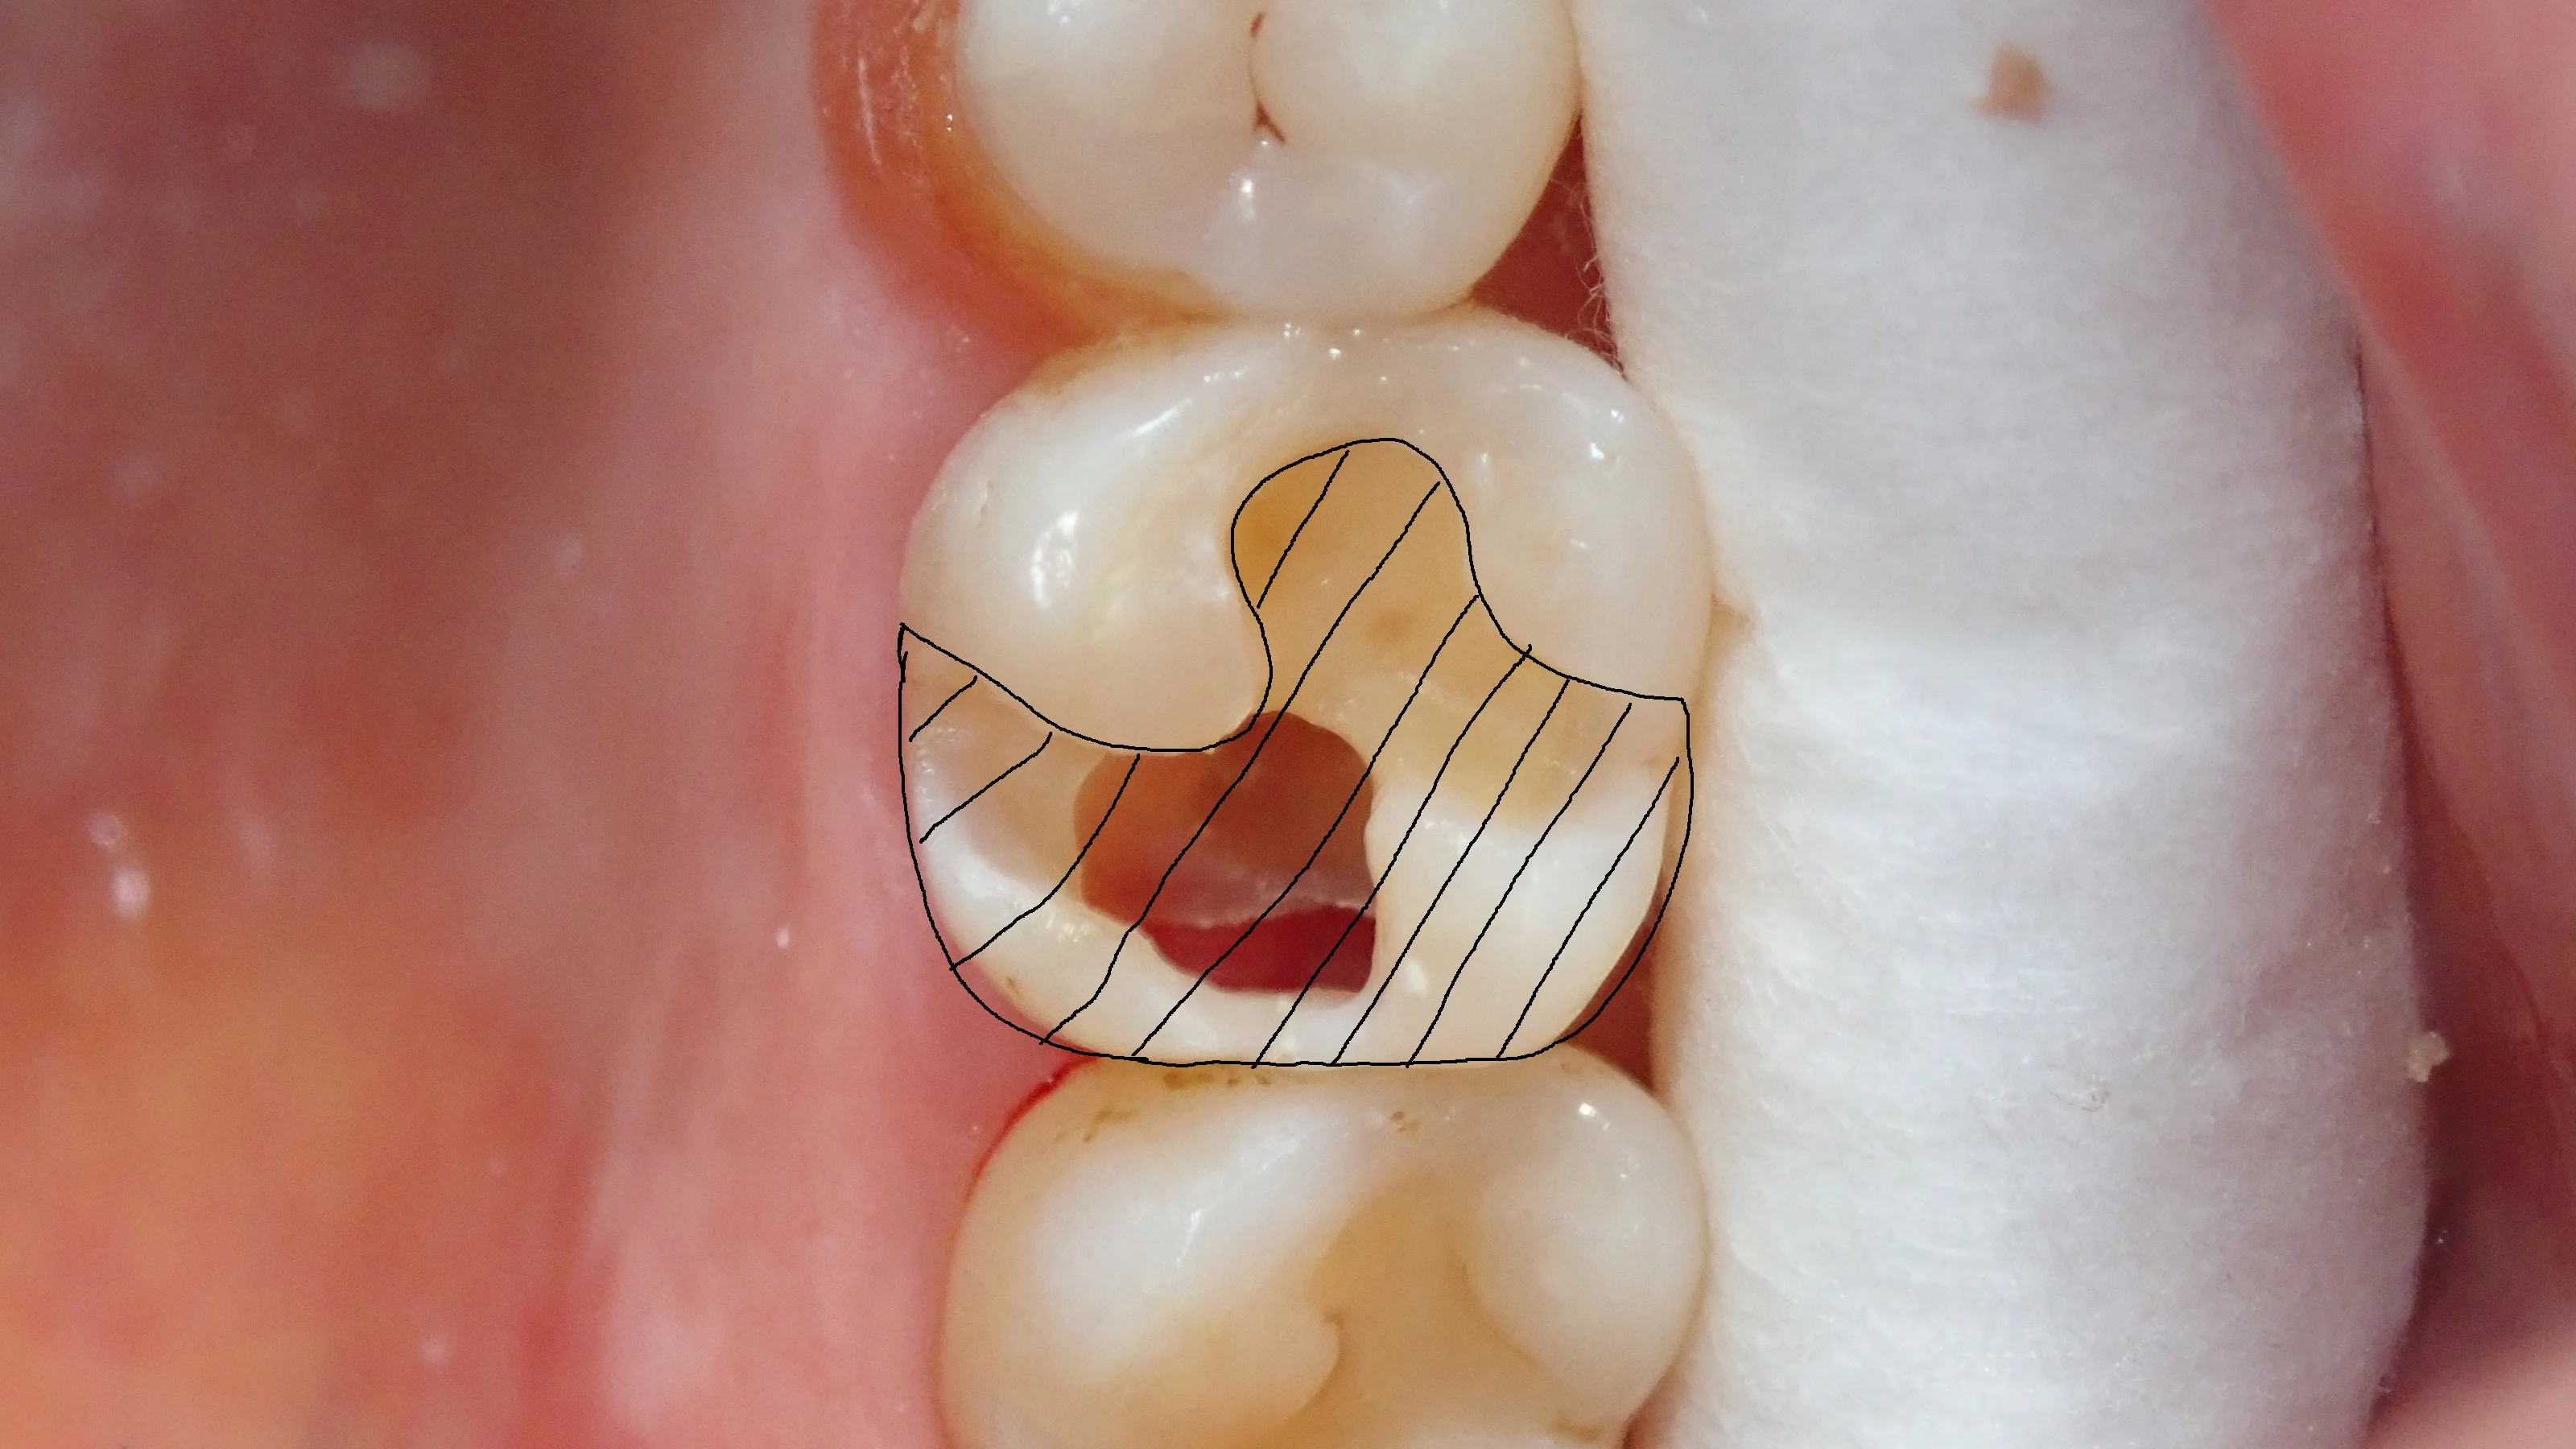

ちなみに、これ、従来の治療(メタルインレー・セラミックインレー)で治そうとすると・・・

こんな感じで、歯のほとんどを削り取る羽目になります。

・インレーにすると歯を大きく失ってしまう事となる